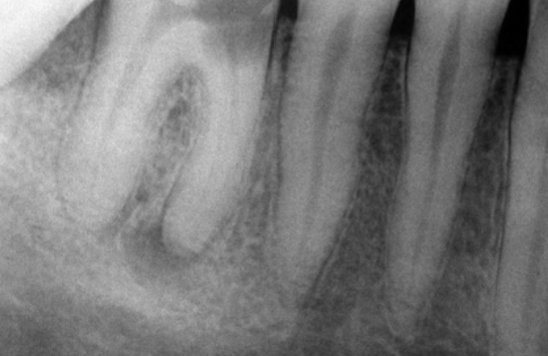

What is the dental anomaly?

Healing Cyst

What are the Radiographic Characteristics of this Healing Cyst?

New bone forms at the original cortex and grows toward the center